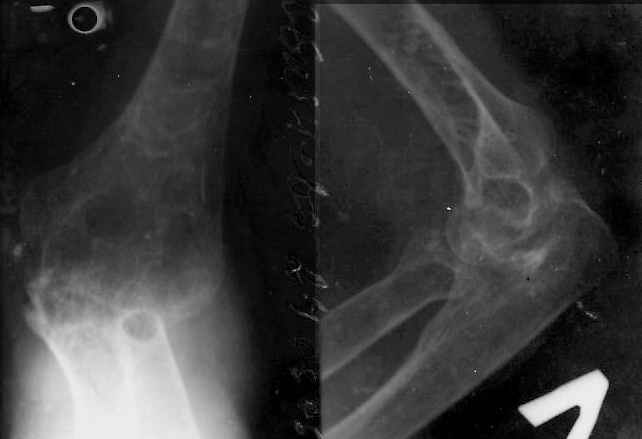

Женщина 45 лет, артистка оперного театра. С ее слов 15.02.2001 г. попала под автобус, был открытый перелом с/3 левой плечевой кости, скальпированная рана плечевой и локтевой области.

Дважды оперировали по месту жительства. На данный момент больная жалуется на практически отсутствие движений в локтевом суставе и тугоподвижность в пальцах левой кисти.

Просила узнать, где можно выполнить операцию эндопротезирование локтевого сустава и косметическую операцию. В пределах какой суммы это ей обойдется.